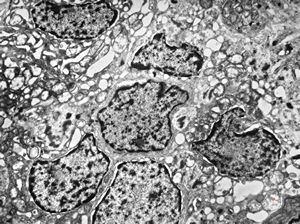

F,12y. | hypertrophic (onion bulb) neuropathy - n.suralis

F,12y. | hypertrophic (onion bulb) neuropathy - n.suralis

F,12y. | hypertrophic (onion bulb) neuropathy - n.suralis